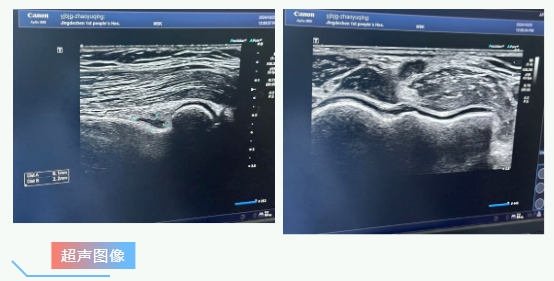

超声诊断:

肱骨小头滑膜增厚

前隐窝积液

腕关节腱鞘炎并食指、中指屈肌肌腱周围积液

肌骨超声是近年来新兴的超声检查技术,是一种应用高频探头来诊断肌肉骨骼系统疾病的检查方法,能够清晰显示四肢的关节腔、肌肉、肌腱、韧带、周围神经等浅表软组织结构及其发生的病变,如炎症、积液、肿瘤、损伤、畸形引起的结构异常。